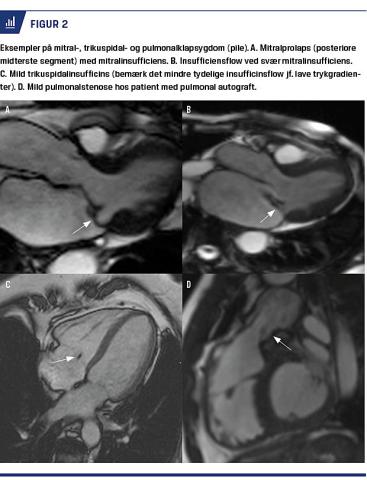

MITRALSTENOSE OG HØJRESIDIGE KLAPSTENOSER

Pulmonal- og trikuspidalstenose (PS og TS) er oftest medfødt og vurderes primært med billeddannelse af klapper og tilstødende kamre. PS kvantificeres med transtorakal ekkokardiografi med CW-Doppler, men særligt ved suboptimalt ekkovindue vil man ved undersøgelse af patienter med PS ofte supplere med CMR, der ikke er begrænset af skanningsplan. Stenosen og særligt dens relation til klappen (prævalvulær, valvulær eller postvalvulær) dokumenteres med CMR (Figur 2), idet man til støtte for undersøgelsen samtidigt opmåler evt. poststenotisk dilatation af pulmonalarterier. PS’ og TS’ sværhedsgrad vurderes samtidigt ud fra volumen/dimensioner af systemvener og højresidige kamre samt højre ventrikel (RV)’s hypertrofi og funktion. Ved suboptimalt indblik ved ekkokardiografi kan trykgradienten over pulmonalklappen opmåles med fasekontrasthastighedssekvenser.

Mitralinsufficiens

Akut, svær MI med lungeødem kan opstå ved chordaruptur eller endokarditis, men de fleste patienter med MI har et langt symptomfrit forløb efter mitralprolaps (myksødematøs omdannelse af mitral cuspis, Barlows sygdom) evt. med »flail-patologi« (bagudbøjning af mitral cuspis). Samlet vurderes MI-graden semikvantitativt ud fra ekkoparametre. Den vigtigste patofysiologiske parameter ved MI er størrelsen af MI ReVol, der med ekkokardiografi forsøges bestemt med PISA-teknik. Svær MI er associeret med LV-dilatation og remodellering samt til sidst kompromitteret kontraktil funktion [24]. Korrektiv kirurgi skal derfor times rigtig, da man ved for sen klapoperation risikerer irreversibel LV-dysfunktion [25, 26]. Mitralklappen bevæger sig betragteligt under systole, og selvom det er muligt med CMR at måle ReVol direkte over klappen (med valve tracking-teknik), bestemmer man normalt ReVol indirekte, typisk som differencen mellem LV-slagvolumen og aortaflow [27]. Cuspispatologi af betydning for prognose og operationsteknik kan oftest ses på CMR-filmsekvenser, men transøsofageal ekkokardiografi er guldstandard. LGE-undersøgelse giver information om anden årsag til LV-dilatation, f.eks. tidligere AMI. Der er endnu kun få kliniske CMR studier af patienter med MI. Et engelsk CMR-studie med patienter med primær MI har vist, at ReVol og regurgitationsfraktion > hhv. 55 ml og > 40% er forbundet med nødvendighed af operation inden for få år ud fra konventionelle kriterier [28]. Et dansk-